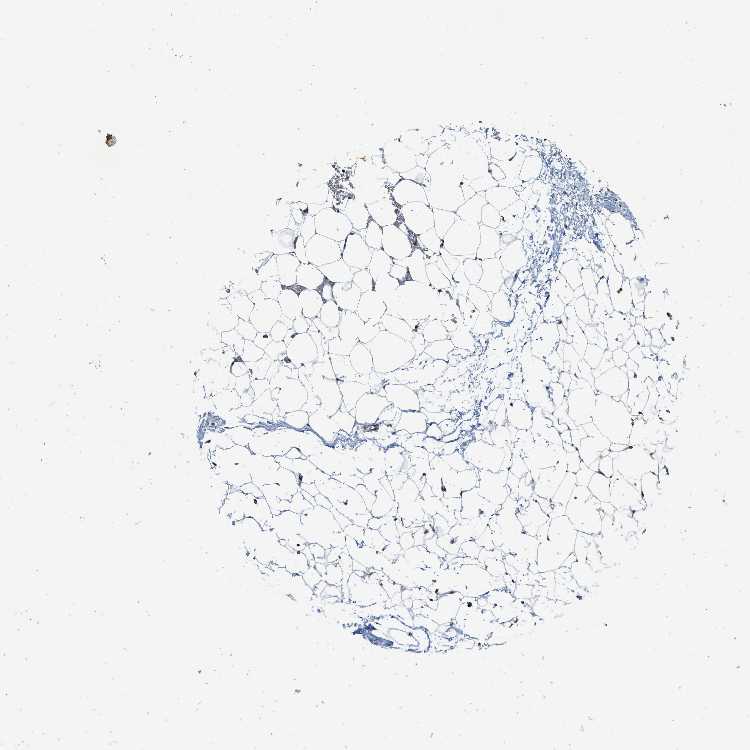

SOFT TISSUE 1 - Antibody stainingi

Antibody staining in the annotated cell types in the current human tissue is reported as not detected, low, medium, or high, based on conventional immunohistochemistry profiling in selected tissues. This score is based on the combination of the staining intensity and fraction of stained cells.

Each image is clickable and will lead to virtual microscopy that enables deeper exploration of all samples and also displays staining intensity scores, fraction scores and subcellular localization as well as patient and tissue information for each sample.

Antibody CAB018724

Fibroblasts Medium

Peripheral nerve Medium